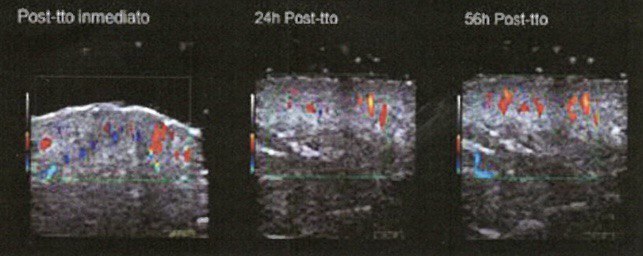

Уменьшение отечности и синяков. После блефаропластики и ринопластики отечность и синяки могут быть распространенными. INDIBA может помочь ускорить устранение отечности и уменьшить синяки, благодаря своей способности улучшать кровообращение и лимфодренаж.

Ускоренное заживление. Процедуры INDIBA способствуют активации естественных процессов регенерации кожи и тканей, что может способствовать более быстрому и эффективному заживлению после разрезов и инъекций.

Одной из ключевых особенностей аппарата INDIBA является способность работать в режиме субтермии (низкотемпературный режим), что позволяет врачам начинать обрабатывать зону хирургического вмешательства прямо в день операции. Это способствует более быстрому заживлению и снижению отечности, что особенно важно после пластических вмешательств.Безопасность и комфорт